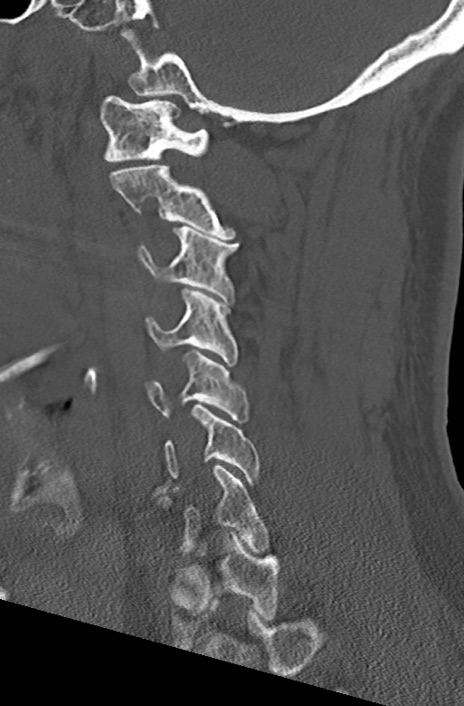

頚椎CT

矢状断像と横断像